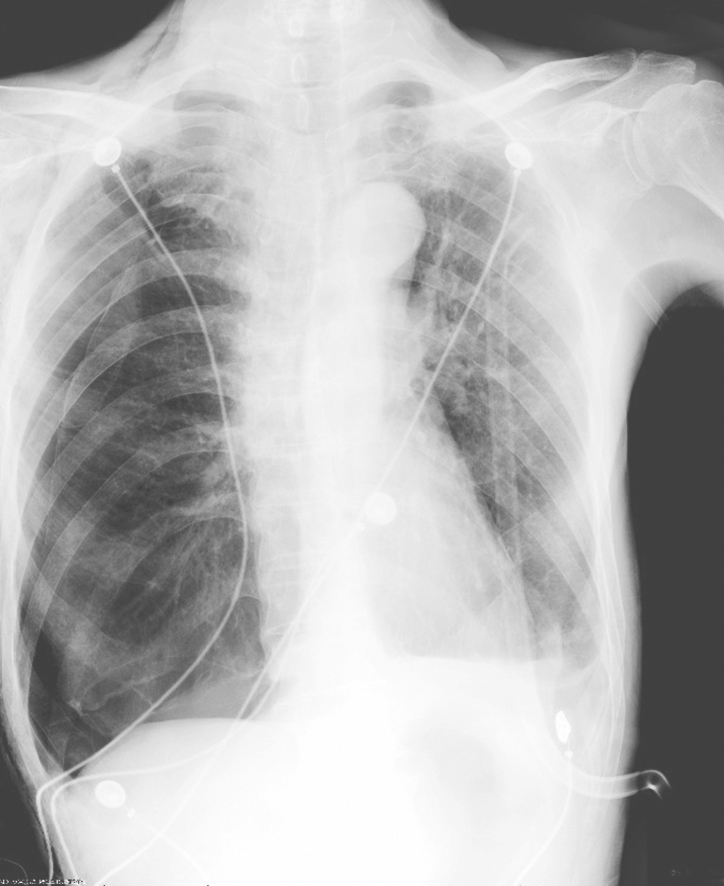

胸腔积液量在0.3~0.5L时,X线仅见肋膈角变钝;积液量多时显示外高、内低、凹面向上的积液影。平卧时积液影散开,使整个肺野透亮度降低。液气胸时可见气液平。大量积液时,纵隔推向健侧,患侧肺野透光度减低。积液包裹时可见边缘光滑的阴影,不随体位改变而变化(图2-13-2)。

图2-13-2 渗出性胸膜炎胸片